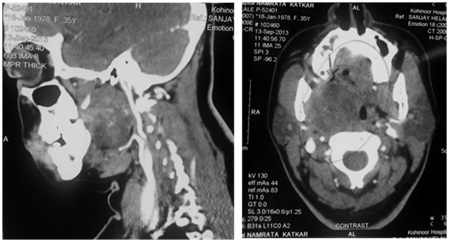

On examination, there was fullness in right peritonsillar fossa, leading to bulge of adjacent, tonsil, soft palate, and uvula because of mass effect. There was no pain or tenderness on palpation or by movement of neck. Hematological and biochemical investigations were all within normal limits. CT scan showed an encapsulated, well marginated, smooth-bordered, mixed density mass in the right parapharyngeal space, and there was no involvement of any vascular or nervous structures. The tumor was 4.0 x 4.0 x 5.0cm and situated in the parapharyngeal space posterior to pterygoid plates and anterior to styloid process (Figure 1A&B).

Figure 1 (A) CT scan with Contrast (Coronal section) - Well defined mildly enhancing Parapharyngeal lesion. (B) CT scan with Contrast- Axial section Parapharyngeal lesion not involving the great vessels and parotid gland.